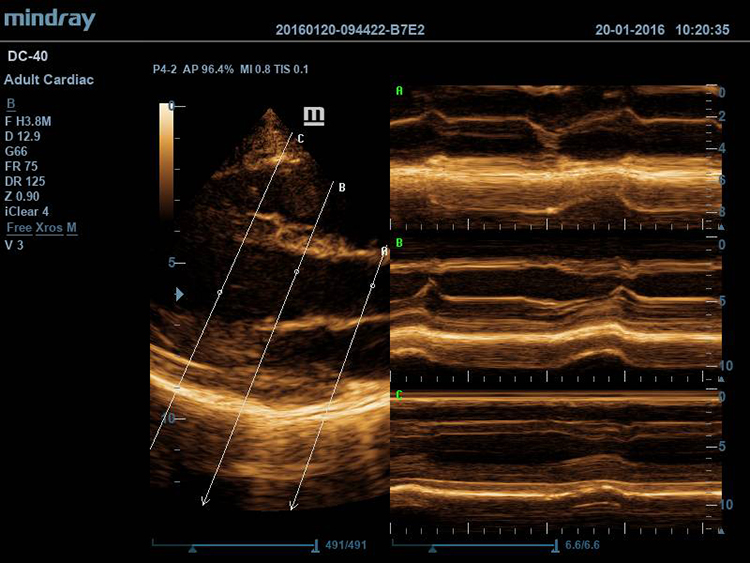

Free Xros M

Точные анатомические измерения с помощью линейных шаблонов, одновременно можно использовать до 3 шт.

Free Xros CM

Детальная информация о сокращении и синхронизации миокарда по фазам благодаря высокой частоте кадров.

Секторный фазированный датчик P4-2, 1,3 - 4,5 МГц